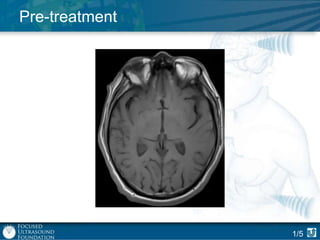

Pre-treatment

1/5